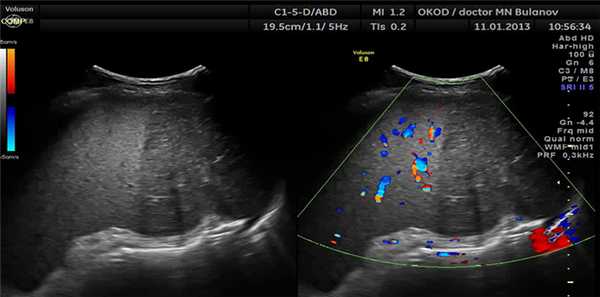

Аневризма селезеночной артерии на УЗИ

Эти аневризмы, лежащие близко к воротам селезенки, могут имитировать кисты селезенки, однако при тщательном внимании к деталям и с использованием цветного допплера природа этих кист станет очевидной.

Варикоз селезеночной вены при ультразвуковом исследовании

Варикозное расширение вен селезенки, вызванное тромбозом селезеночной вены или портальной гипертензией, проявляется как змеевидные кистозные пространства. Тщательное сканирование должно выявить другие признаки портальной гипертензии или тромбоза селезеночной вены. Часто бывает спленомегалия. Допплерография помогает диагностировать данную патологию.